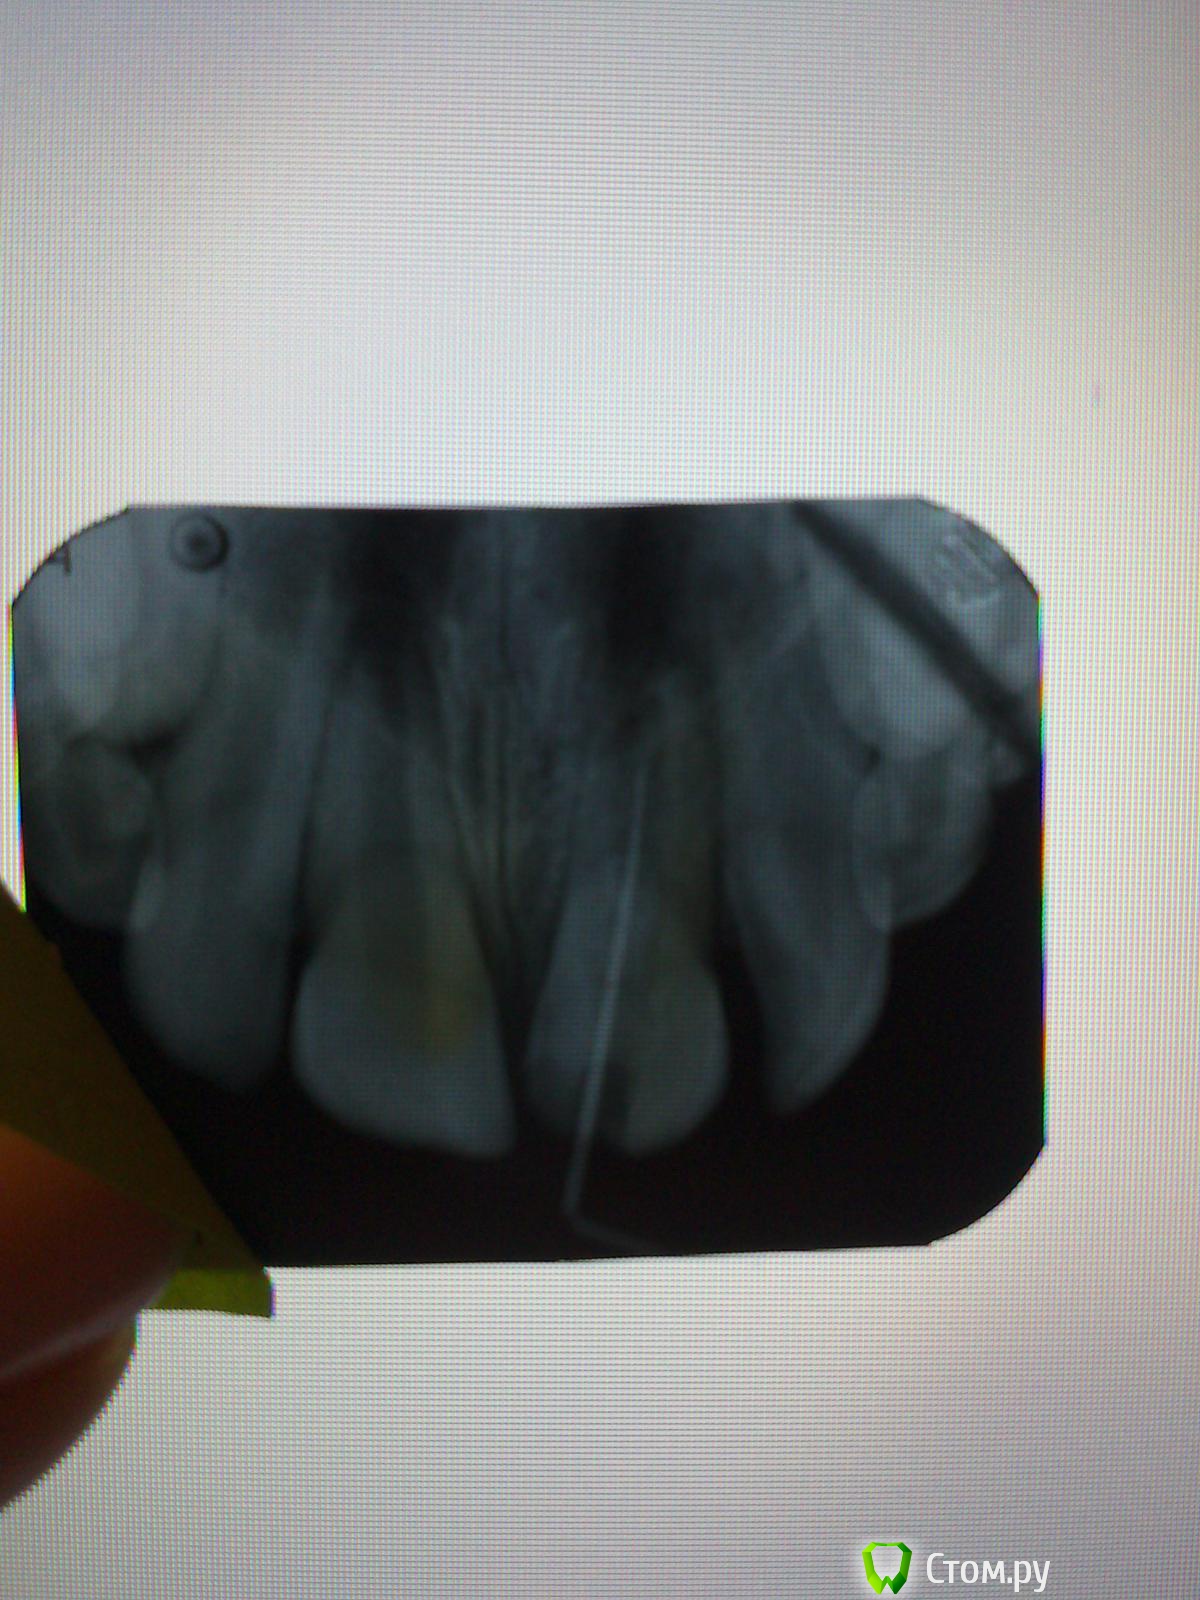

Kykysyavika Опубликовано 28 января, 2014 Автор Поделиться Опубликовано 28 января, 2014 (изменено) А вот пациент №2. 9 лет, тоже травма.Обратились еще летом Веду на Метапасте. Снимок почти через полгода.Никакой динамики, по-моему. Изменено 28 января, 2014 пользователем Kykysyavika Ссылка на комментарий

Kolchanov Опубликовано 28 января, 2014 Поделиться Опубликовано 28 января, 2014 (изменено) Последний случай лучше передать. Я думаю в Краснодаре есть эндодонтисты-микроскописты.Ну, если только аденьгия и пофигия родителей присутствует, то можно самой. В принципе, в такую трубу можно и без оптики заглянуть. Нужен фонарик мощный на лоб и зеркало FS. Триоксидент, Взять толстую конусную гуттаперчу и обратным концом утрамбовывать, предварительно отмерив длину. До половины канала им, а дальше закомпозитить.Разумеется,перед этим все намыть как следует с ультразвуком.Хотя, лучше найти микроскописта, договориться, заплатить за пациента свои и иметь возможность постоять рядом и поглазеть-поспрашивать Пройдитесь по форуму. Вдруг кому из Краснодарских случай такой клинический в коллекцию нужен Изменено 28 января, 2014 пользователем Kolchanov Ссылка на комментарий

Kykysyavika Опубликовано 28 января, 2014 Автор Поделиться Опубликовано 28 января, 2014 Последний случай лучше передать. Я думаю в Краснодаре есть эндодонтисты-микроскописты.Ну, если только аденьгия и пофигия родителей присутствует, то можно самой. В принципе, в такую трубу можно и без оптики заглянуть. Нужен фонарик мощный на лоб и зеркало FS. Триоксидент, Взять толстую конусную гуттаперчу и обратным концом утрамбовывать, предварительно отмерив длину. До половины канала им, а дальше закомпозитить.Разумеется,перед этим все намыть как следует с ультразвуком.Хотя, лучше найти микроскописта, договориться, заплатить за пациента свои и иметь возможность постоять рядом и поглазеть-поспрашивать Пройдитесь по форуму. Вдруг кому из Краснодарских случай такой клинический в коллекцию нужен Наверняка есть специалисты-эндодонтисты-микроскописты, я не думала над этим. А таких клин.случаев, наверняка. хватает. Я МТА боюсь, а если натрамбую туда больше,чем нужно?Я была на лекции, видела такие зубы, пломбированные Триоксидентом, все красиво, хорошо и после лечения все гуд. Но сама я боюсь... В случае обострения как быть? Ссылка на комментарий

Kolchanov Опубликовано 28 января, 2014 Поделиться Опубликовано 28 января, 2014 (изменено) Обострение дает выталкивание инфицированного дентина, остатков пульпы, еды из открытых зубов и т.п. Триоксидент обострения не даст и от избыточного выталкивания ничего не будет.В такой трубе не надо ничего скоблить, там и так тканей зуба нет. Только мыть, мыть, мыть. Зубы у пацана есть, можно коффер соорудить без всего. Порезать перчатку, заколхозить рамку, прожечь дырку зондом, закрепить резиновым шнуром между зубами. Мыть станет удобнее. Но это все тухлый энтузиазм Лучше перетереть с родителями, сказать, что чадо будет через некоторое время еще более щербатое, чем сейчас, если не принять мер. Пусть уже сделают подарок ему на день рождения. Вон Каплан там у вас поблизости почти даром работает. Отправьте ему, у него юниветы (или экзамы? ) дорогие есть хотя бы Изменено 28 января, 2014 пользователем Kolchanov Ссылка на комментарий